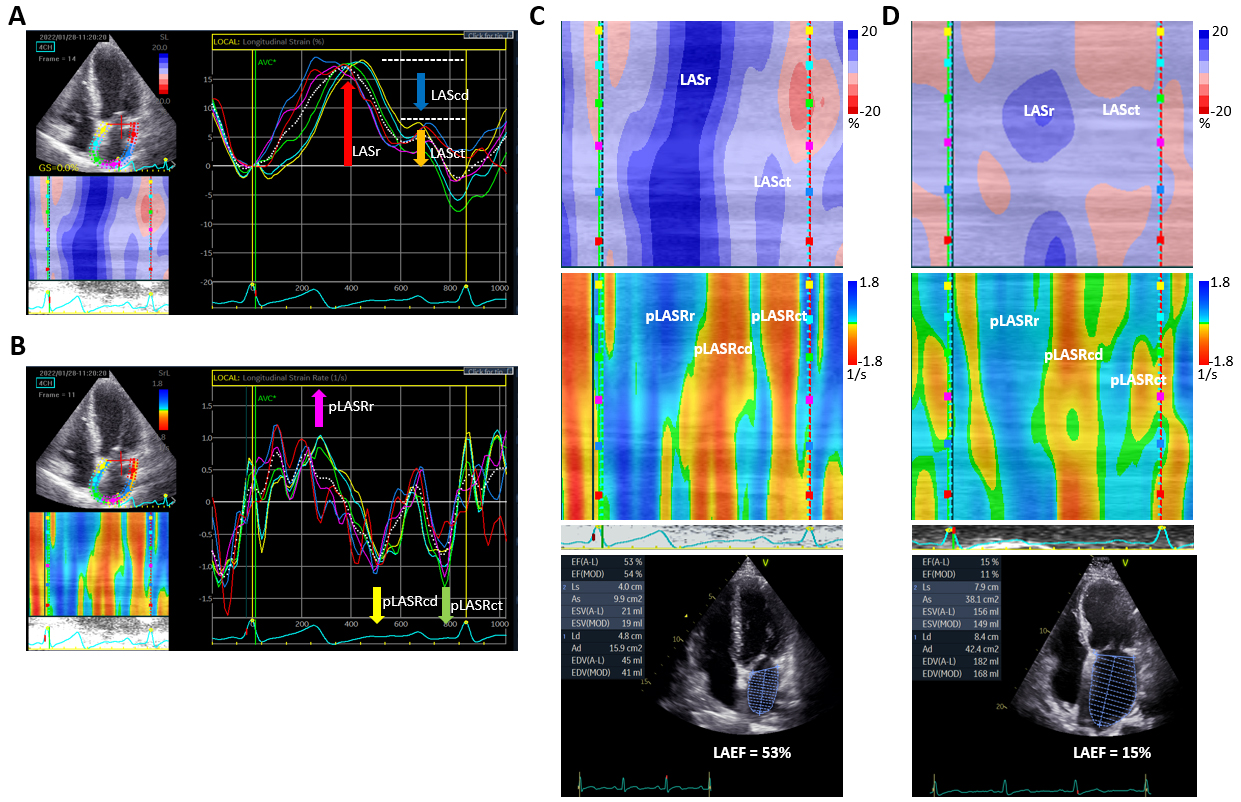

LA electrical and mechanical dysfunction coexist in the early phase before LA enlargement [118]. Sarvari et al. [119] demonstrated that inhomogeneous contraction of the left atrium potentially predicted AF recurrence after ablation. Because STE is angle-independent and can assess regional myocardial function and timing accurately, the regional differences in 2-dimensional (2D) STE-derived LA strain and strain rate potentially could be used to measure heterogeneous LA fibrosis and dysfunction indirectly. LA mechanical dispersion is calculated as the standard deviation in time to peak strain of the LA segments [119]. It is greater in AF patients than in healthy individuals, increases proportionately to the duration of AF [116], and provides prognostic information on the risk of AF recurrence in patients after ablation [116, 119]. In a case-control study, patients with new-onset AF had significantly worse LASr and LASct, and more pronounced LA mechanical dispersion, than those without AF [120]. However, it is time-consuming to calculate the standard deviation for parameters of LA mechanical dispersion because sophisticated mathematics is needed for averaging the 2–3 instances of six segmental values per apical 4-chamber and 2-chamber views (3 peaks of LA strain rate curve in sinus rhythm). Alternatively, the curved M-mode color images of LA strain and strain rate provide detailed spatial and temporal information on LA deformation mechanics. These images provide a unidimensional view of LA strain and strain rate, illustrating the changes in length and in strain/sec of the depicted LA wall along the time axis, respectively. As shown in Fig. 1C–D, the spatial and temporal information of LA deformation can be displayed in these images, on which blue or red color, deep or light hue, and pattern of color distribution indicate the direction, strength, and homogeneity of LA deformation, respectively. However, it is challenging to use visual estimation to precisely differentiate these images. Recently our group demonstrated that a deep convolutional neural network (CNN) analysis can successfully incorporate spatial and temporal features from these STE images into an overall assessment of LA deformation mechanics; indeed, the STE image-based CNN model outperformed the logistic regression model using LAD, LAEF, LA strain, and strain rate in predicting AF recurrence after CA [121]. This study demonstrated the potential advantages of supervised deep learning with CNNs to classify images to provide prognostic information for AF intervention. Note that this retrospective study included only 606 patients, and large prospective studies are needed to optimize CNN model performance. Recently, manufacturers have begun developing dedicated software packages for LA strain measurement after publication of the common standards to assess LA strain [90]. Newly-available softwares, such as AutoStrain (TomTec) or LA Automated Function Imaging (Echo-Pac), allow for a quick assessment of LA strain. Future goals would be to achieve fully automatic generation and interpretation of LA STE images, provide fast and reproducible assessment of LA deformation properties, and validate and enhance the performance of CNN models in this domain.